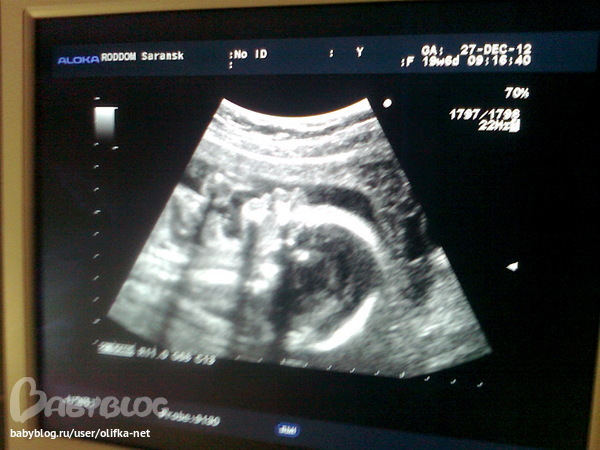

Наше 2-е узи

Узи в самом конце 20 недели.

Малыш в головном предлежании. У нас будет

еще один мальчишечка ))) Папа держись )))

Вот такой вот милый профиль

Бипариетальный размер головы - 49мм.

Лобно-затылочный - 67мм.

Окружность головы - 198мм.

Длина бедреной кости (левой\правой) - 34мм

Длина кости голени (левой\правой) - 32\31мм

Длина плечевой кости (левой\правой) - 34мм

Длина костей предплечья (левой\правой) - 30\27мм

Размеры плода соответствуют 21 недели.

Боковые желудочки N. Большая цестерна N. Мозжечок 22мм. Профиль N. Носогубный четко N. Легкие N. ЖЕлудок N. Кишечник N. 4-х камерный срез сердца четко. ЧСС 144. Индекс амниотонической жидкости 11.9 . Плацента нормальная 23мм. Однородная.

Немного огорчило, что степень зрелости плаценты уже 0-1 (вариант нормы но ни есть гуд). И в области шеи сосуды пуповины. В прошлую беременность малыш родился с двойным обвитиеми плацента старела быстрее положенного . История похоже повторяеться.